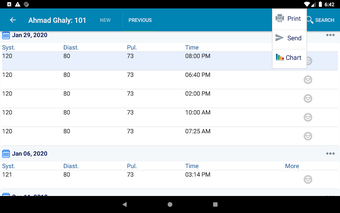

In addition, the app has a blood pressure module that measures systolic, diastolic, and pulse, and allows users to export blood pressure reports to either PDF or graphs. The app also has a blood glucose (sugar) module that records blood sugar values and allows users to export blood glucose reports to either PDF or graphs. Users can also send blood pressure and blood sugar reports to their doctor. The app is compatible with multiple screens, including phones and tablets, and works on Chromebook systems. Overall, the Android Medical Records App is a great tool for patients and physicians alike for managing patient information and medical records.